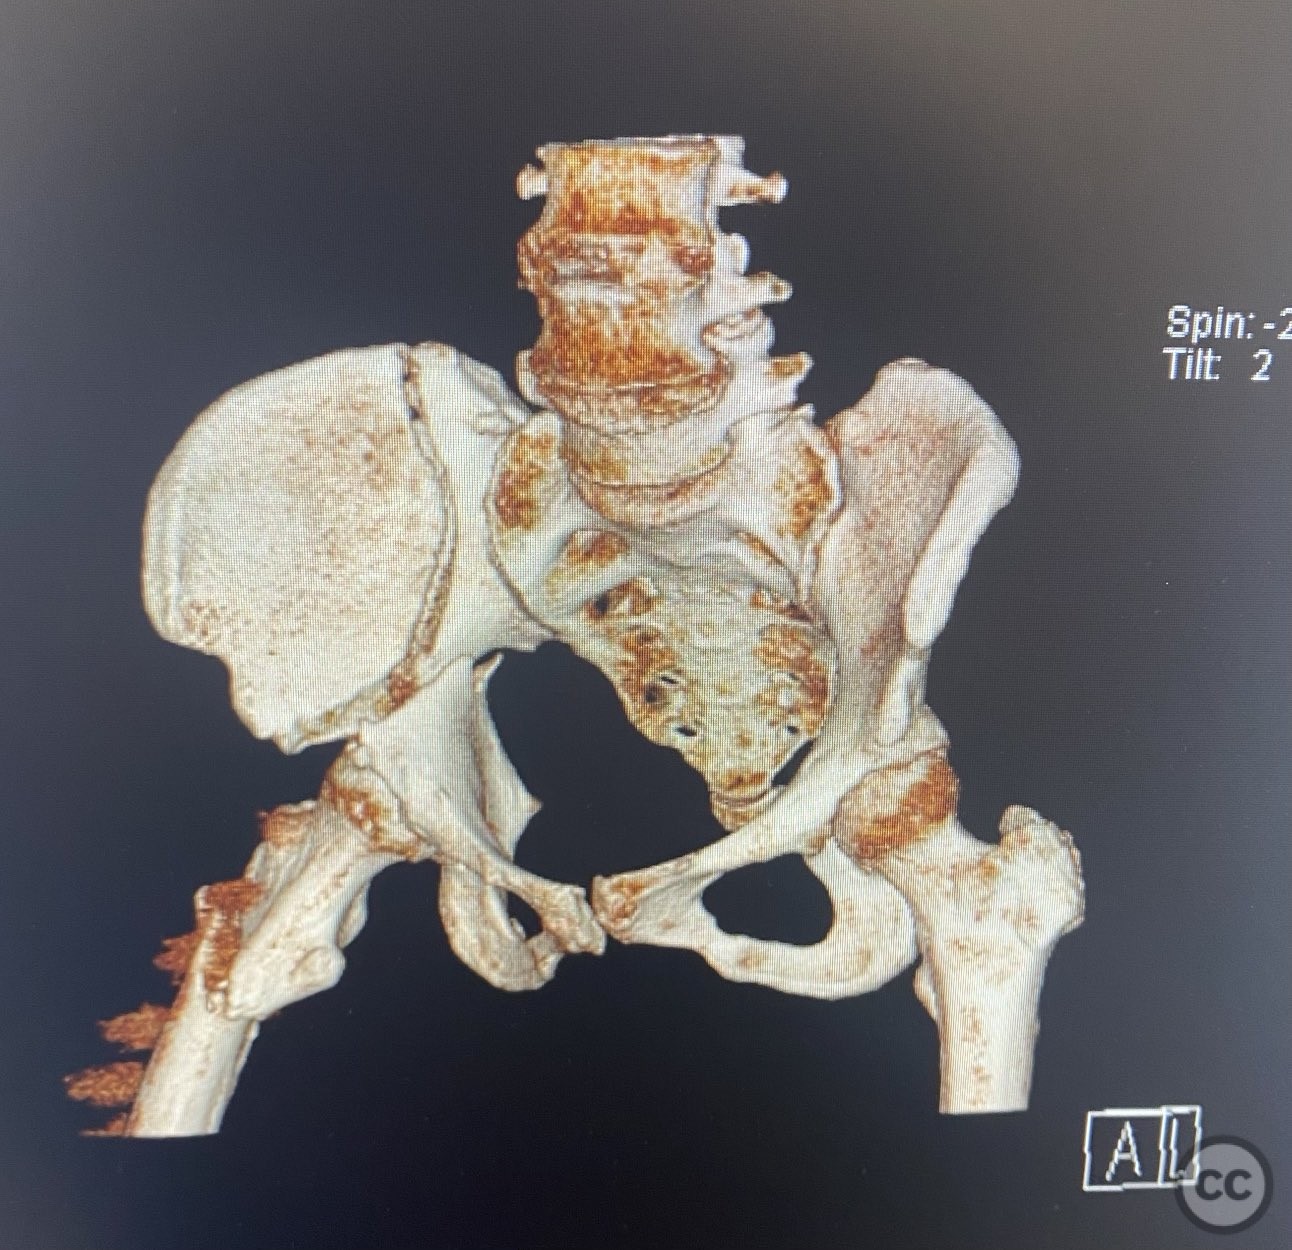

Clinical and radiological findings:  An active but obese senior patient presented with a complex acetabular fracture following a lap belt injury. The patient had significant anterior abdominal surgical scarring from prior gynecological operations. Initial clinical assessment revealed a closed injury with associated soft tissue trauma in the inguinal and lower abdominal regions. Radiographs and computed tomography demonstrated an AO/OTA 62C1 (AsBothCol) pattern, with both anterior and posterior column involvement and displacement. There was no evidence of neurovascular compromise. Notably, the lap belt injury zone showed extensive soft tissue contusion and devitalization.